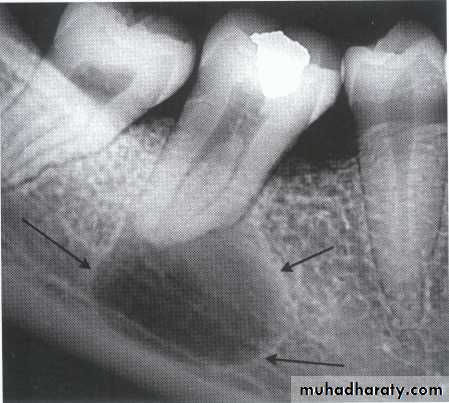

Multilocular appearance, expansion (arrowed) and considerable displacement of the adjacent teeth.

Buccal and lingual expansion (arrowed) and the undulating cortical border.

• Aneurysmal Bone Cyst

Large multilocular aneurysmal bone cyst

in the ramus with marked expansion andthe displacement of/8.

It is non-neoplastic ,exaggerated , localized, proliferative lesion of vascular tissue, containing giant cells.

It’s a variation of the central giant cell granuloma , can be diagnosed only by histological examination